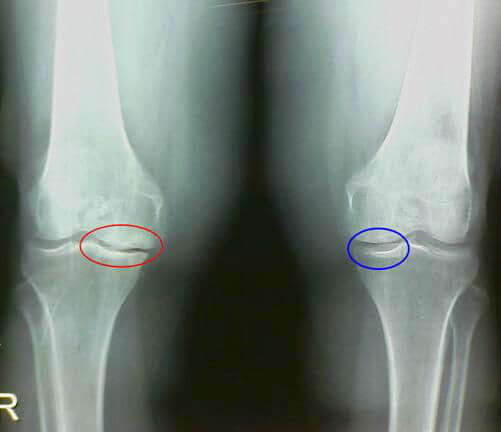

На рентгенологических снимках могут отражаться признаки различной яркости,

что и становится поводом для отнесения остеосклероза к разным стадиям:

- На начальной стадии обнаруживаются краевые разрастания кости. При этом суставная щель на снимке не уменьшена. При осмотре обнаруживается частичное ограничение движений в суставе.

- При дальнейшем развитии патологии снимки показывают существенное разрастание костной ткани и сужение суставной щели. Больные жалуются не только на боли, но и на невозможность выполнять повседневную работу.

- Для запущенной стадии характерна деформация колена с уплощением. Разросшиеся края кости проникают в хрящ и суставную щель, что провоцирует полную потерю подвижности сустава.